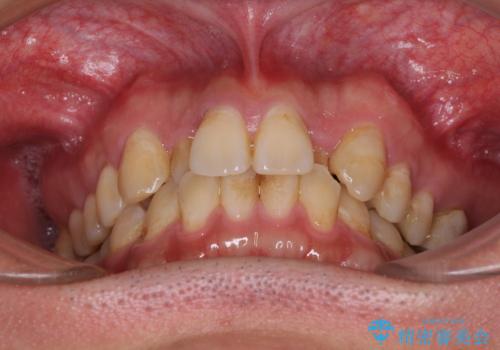

- 虫歯が多く、セラミッククラウンにより虫歯治療を行っている途中で矯正治療をしたいとのことで来院された患者様です。

上顎前歯が舌側に転位しており、なるべく早く楽に矯正したいとのことで、ワイヤー矯正を行うこととしました。